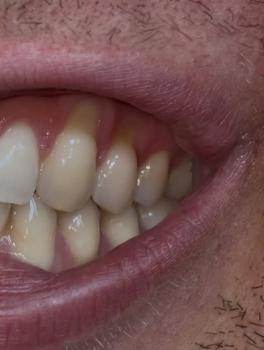

Getting a dental implant after a tooth extraction is one of the most common questions patients ask. The timing depends on your healing, bone condition, and overall oral health.

There are three main options: